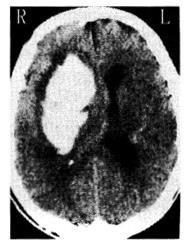

问题 58岁,男性高血压患者。爬山时突发一侧肢体无力。3小时后偏瘫。脑CT见图。

可能的诊断为

选项 A:高血压脑病 B:脑转移瘤 C:脑血栓形成 D:脑出血 E:脑栓塞

答案 D

解析 本题考查目的是综合临床资料,CT图像作出脑血管病的诊断。本病例为急性起病的脑血管疾病。脑血管病分为缺血性卒中和出血性卒中。脑血栓形成、短暂脑缺血发作、脑栓塞均为缺血性卒中范畴。高血压性脑出血为出血性卒中。根据脑缺血性卒中和出血性卒中的鉴别诊断表。可以得出高血压性脑出血为正确答案。脑转移癌起病较慢,而且CT的病灶周围有大片水肿,为迷惑答案。